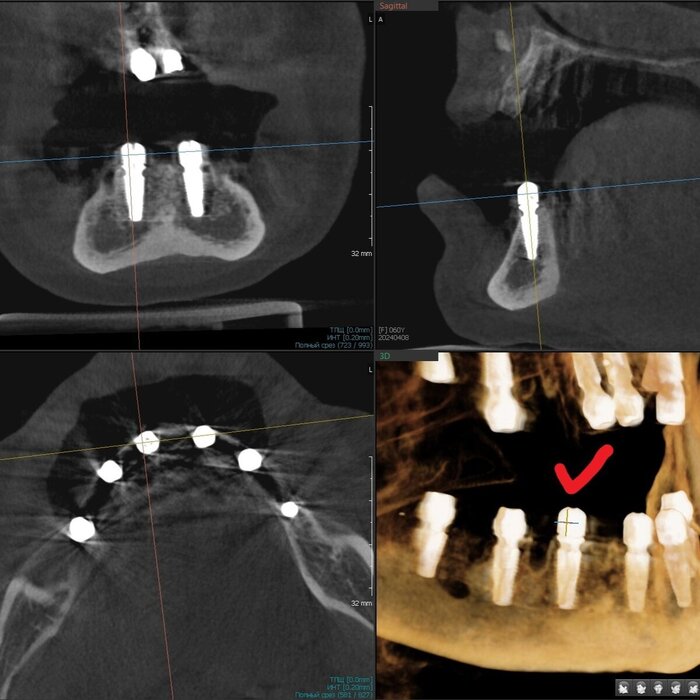

Получилось так, что сверху всего 8 зубов, по 4 с каждой стороны. Чёрная точка (которую вы точно увидите, скос эмали на зубе 1.1) - конструктивные особенности, всё это будет закрыто пломбировочным материалом. Зуб 1.1 - дополнительный имлантат, который потом планируем убрать. Он нужен лишь для усиления, ибо торк полноценный был получен только на одном из остальных 6-ти установленных.

Напоминаю - протезы временные адаптационные

Так же важный момент - верхний протез соприкасается с нижним только в точках полученного торка (их всего 2), остальное "на весу" и жевать не способно.